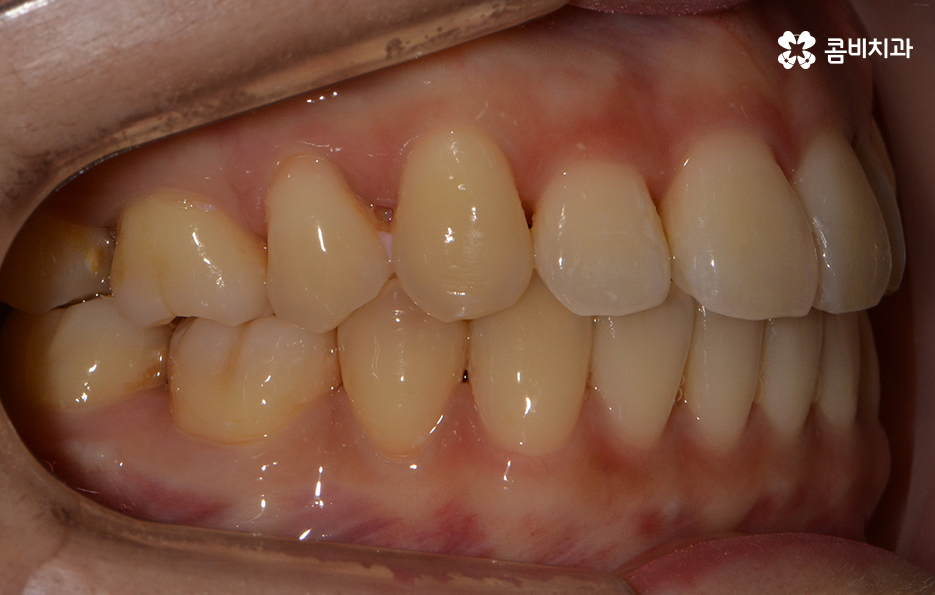

돌출된 앞니로 인해서 교정을 원하신 상황이며 치료 전 치아 상태

치열의 상태가 정면으로 바라봤을 때 비교적 가지런한 편이지만

측면으로 볼 때 유독 앞으로 돌출된 경우라면

입모양과 얼굴형에도 영향을 주기 때문에

치료가 시작되기 전 치아 상태

돌출치아로 인한 돌출입이나 앞니의 벌어짐이 비교적 심하지